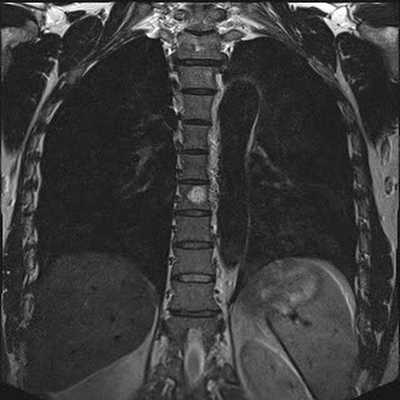

МРТ грудного отдела позвоночника в коронарной проекции

В результате томографии врач получает серию послойных изображений спины, выполненных в аксиальной, сагиттальной и фронтальной проекциях. На основании полученных фото возможно построение 3D-модели изучаемой зоны.

Гемангиома на МРТ грудного отдела позвоночника, коронарная проекция

Оценивая состояние грудного отдела, врач указывает локализацию возможных патологических очагов в соответствии с названием расположенного рядом позвонка (Th1-12). Протокол исследования содержит информацию о размерах измененного участка, интенсивности сигнала и природе заболевания.